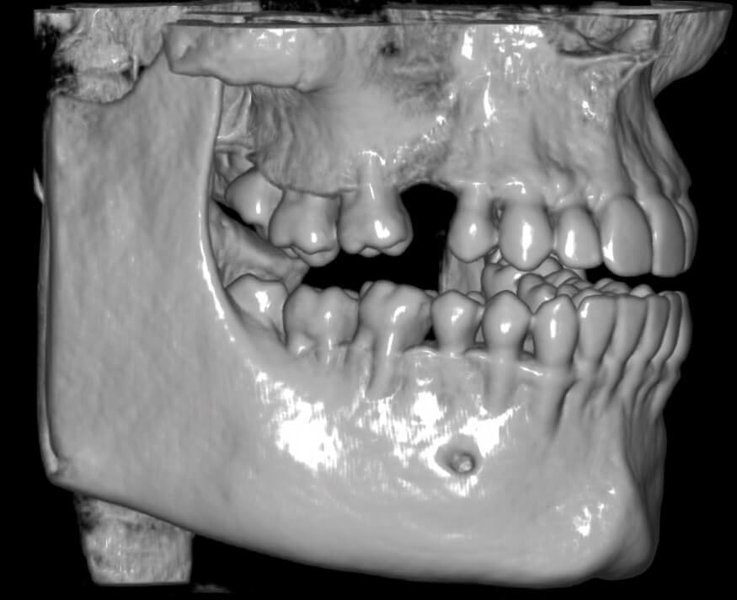

КОМПЛЕКСНЫЙ ГИБРИДНЫЙ КЛКТ ДЛЯ 2D/3D ВИЗУАЛИЗАЦИИ. ИЗОБРАЖЕНИЯ В ВЫСОКОМ РАЗРЕШЕНИИ С ЗАХВАТОМ МЕЛЬЧАЙШИХ ДЕТАЛЕЙ

GIANO HR – универсальное обновляемое устройство от NewTom для всех задач, связанных с радиографией. Благодаря полному диапазону опций 2D и 3D исследования для стоматологии оно предлагает множество особых трехмерных обследований для челюстно-лицевой хирургии, оториноларингологии и осмотра шейного отдела позвоночника. Визуализация только наивысшего качества с технологиями и опытом NewTom

NewTom GiANO HR новейшая модель была официально представлена на международном конгрессе радиологов ECR 2018 в марте в Вене. Благодаря обновленным системам механики и запатентованным механизмам работы аппарат отличается от своих сверстников Высочайшим качеством получаемых изображений, как 2D, так и 3D. Лучшее качество снимков и мы отвечаем за это! Этот аппарат заменит три аппарата! Панорамный аппарат, цефалометрическая приставка и конусно-лучевая компьютерная томография интегрированы в единую платформу. В комплекте детектор для выполнения 3D исследований с захватом области 13х16 см, Сьемный 2D CMOS детектор для выполнения панорамных исследований, и ТРГ.